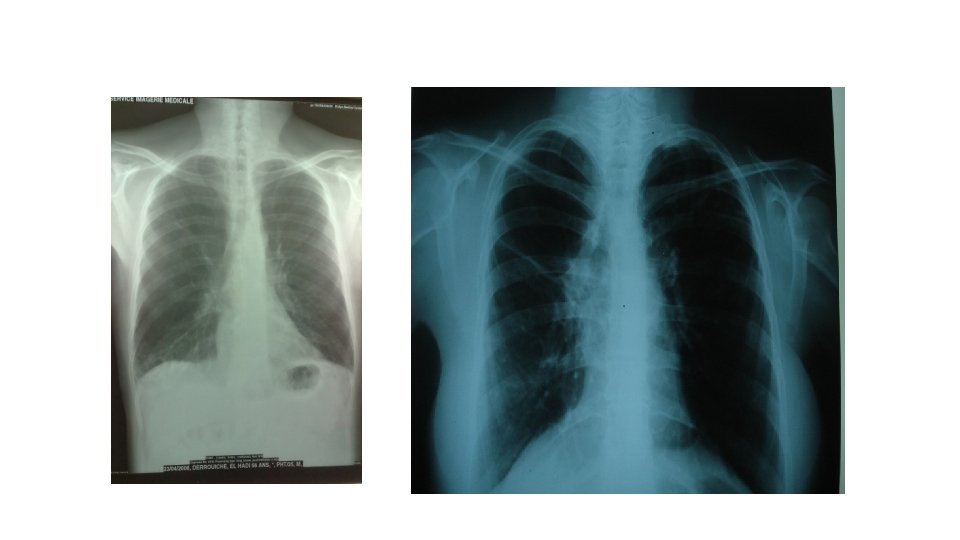

Les tumeurs malignes: tumeurs primitives • Image en patte de crabe

• Opacité ronde à limite irrégulière

• Opacité apicale

• Opacité excavée( image en plage, image cavitaire, image mixte à limite interne anfractueuse, image en cadre)

Les tumeurs malignes: métastases • Image en lacher de ballon